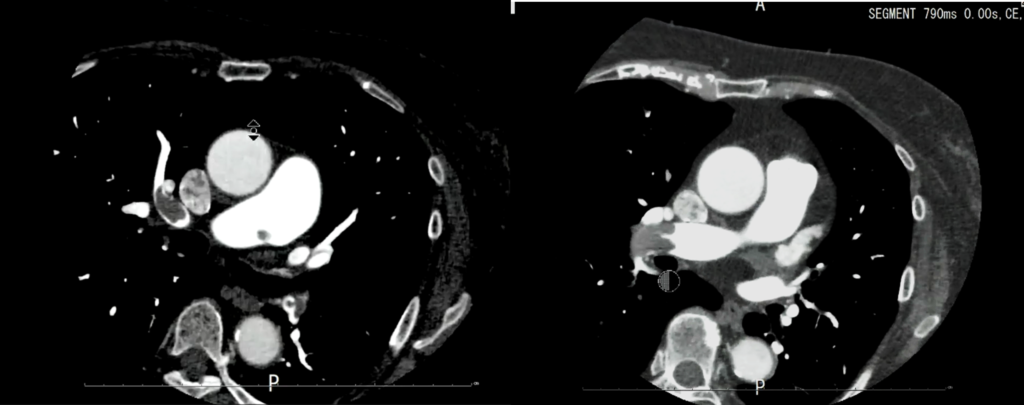

120kvで撮影した時の造影剤のCT値を1とした時の相対値では低電圧にするとCT値が1.6と上がり、120kvでの撮影した時と同じ造影効果を得るために必要な造影剤量も62%と減らせます。

実際の画像ですが、

120kV と比べるとCTは上がっていることがわかります。

当院の臨床画像でも

80kvで撮影した方がDVTの描出が良くなっています。

その他にも低電圧で撮影するので光子量が減るため、被ばく量が少なくなるというメリットもありますが、ただし注意が必要なのは電圧を下げることによって透過するエネルギーが低くなるので120kvと比較するとノイズが多くなります。